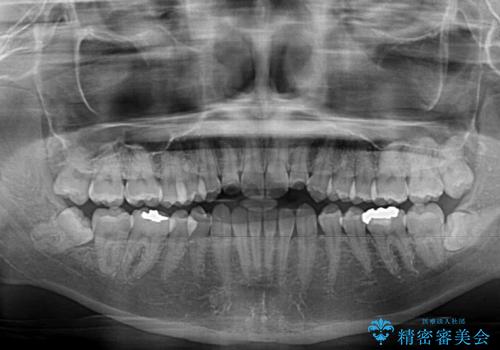

前歯のクロスバイト インビザラインによる矯正治療

- 前歯のクロスバイトとデコボコを気にして来院された患者様です。

骨格的に下顎前突傾向であるため、自己管理が煩わしくないようであれば、インビザラインによる矯正治療がお勧めとなります。

インビザラインを用い、下顎歯列を後方に移動させながら全市の被蓋を改善し、歯並びを整えていくこととしました。